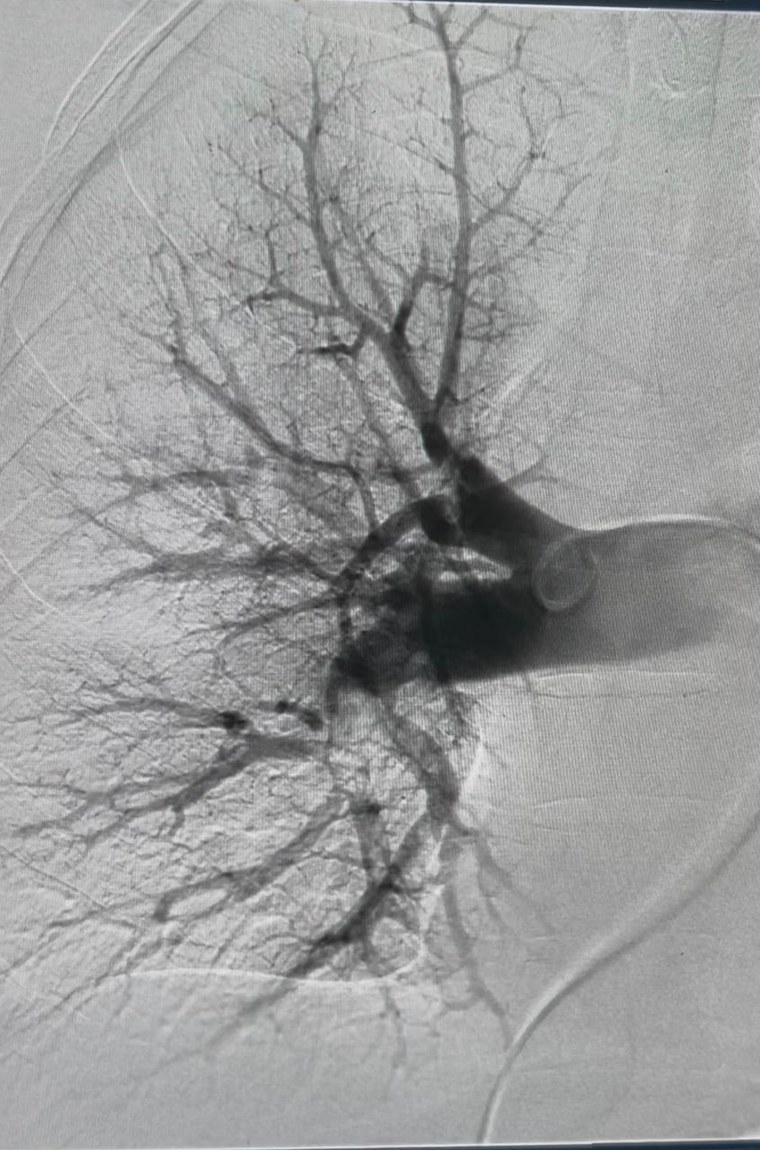

Isaac deu entrada na unidade com queixa de dor respiratória e, após avaliação clínica e exames de imagem, foi confirmada a presença de um coágulo de grandes proporções obstruindo a circulação nos vasos do pulmão. A obstrução comprometia o fluxo sanguíneo adequado, o que levou à indicação imediata da trombectomia mecânica pulmonar.

Segundo o cardiologista intervencionista Jean Santiago, a trombectomia mecânica pulmonar consiste na retirada do coágulo de sangue diretamente da artéria pulmonar, permitindo o restabelecimento do fluxo sanguíneo normal. O procedimento foi realizado em caráter de urgência e teve êxito, possibilitando a rápida estabilização do quadro clínico do paciente, que segue em programação de alta hospitalar.